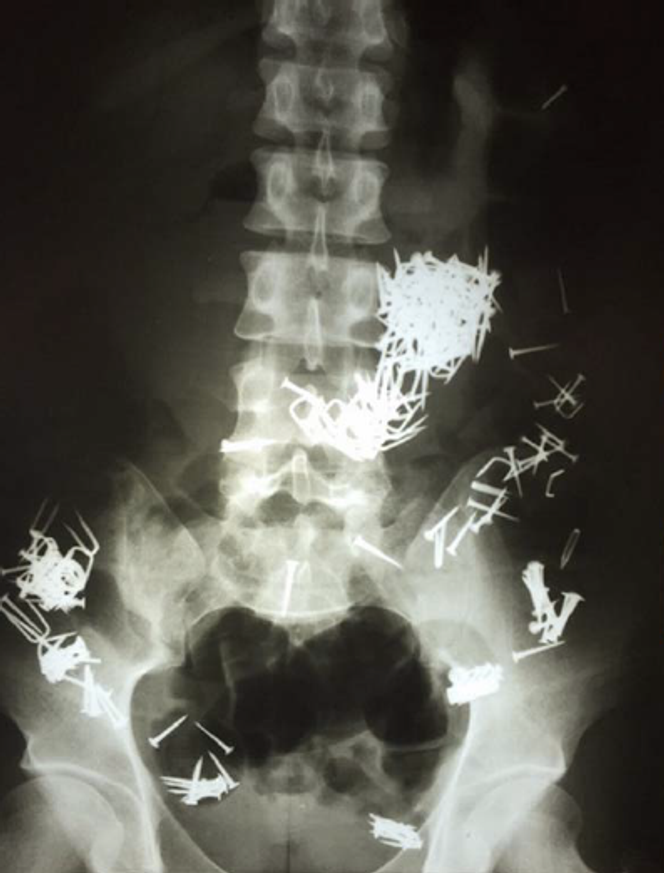

Radiographie abdominale révélant la présence de nombreux clous et vis disséminés dans le tube digestif. Certains objets sont moulés à la forme de l’estomac pour former un gros bézoard, tandis que d’autres sont agglomérés dans le côlon.

Comme souvent, c’est l’imagerie qui change tout. Une radiographie thoraco-abdominale est réalisée. Elle met en évidence une image stupéfiante : une multitude d’objets métalliques disséminés dans l’ensemble du tube digestif. Certains sont regroupés dans l’estomac, formant une masse compacte, tandis que d’autres sont éparpillés dans l’intestin.

Interrogé en langue des signes, le patient finit par avouer avoir avalé des clous, des vis, des écrous et du fil métallique… neuf jours auparavant. Il est impossible de savoir s’il les a ingérés en une seule fois ou progressivement. L’homme souffre de troubles psychiatriques sévères, avec plusieurs antécédents de gestes auto-agressifs.

Ce qui frappe alors, c’est le contraste entre la gravité potentielle de la situation et l’absence de symptômes : pas de douleur abdominale, pas de vomissements sanglants, pas de saignement rectal, pas de signe d’occlusion intestinale. Devant le nombre d’objets, leur dispersion et leur caractère dangereux, les chirurgiens décident d’intervenir, craignant une perforation digestive ou la survenue d’une péritonite.